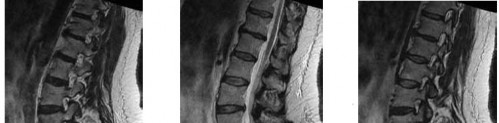

Question 16

A 60-year-old Japanese male presents with progressive clumsiness of his hands, difficulty walking, and hyperreflexia in both upper and lower extremities. Lateral cervical radiograph reveals dense ossification extending vertically along the posterior aspect of the C3 to C6 vertebral bodies. Which surgical approach is generally preferred if the canal occupying ratio is 60% and cervical alignment is lordotic?

Explanation